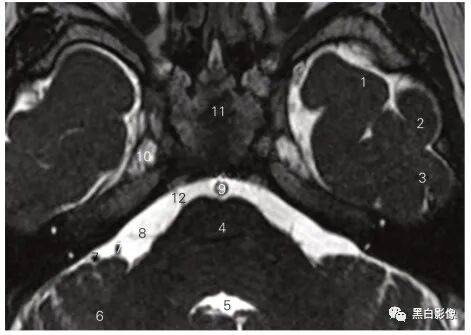

图5-2 经视神经的冠状断层MR T2加权图像

1 眼动脉 ophthalmic artery 2 外直肌 lateral rectus

3 视神经鞘 sheath of the optic nerve

4 筛骨鸡冠 crista galli of ethmoid bone

5 下直肌 inferior rectus 6 内直肌 medial rectus

7 蛛网膜下隙 subarachnoid space 8 视神经 optic nerve

9 眼上静脉 superior ophthalmic vein